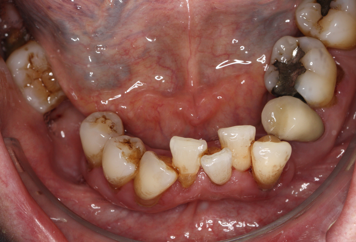

Local plaque retentive factors

Image shows crowded lower anterior teeth with supragingival calculus and staining.

Local plaque-retentive factors, such as calculus, mal-positioned teeth, overhanging restorations, crown and bridgework, partial dentures and fixed and removable orthodontic appliances can complicate or hinder plaque biofilm removal in the area, increase the risk of gingival and periodontal inflammation and are a risk factor for disease (see figure: Local plaque retentive factors). Where supragingival calculus deposits are present, removal of these may be necessary for effective personal oral hygiene to be achieved.